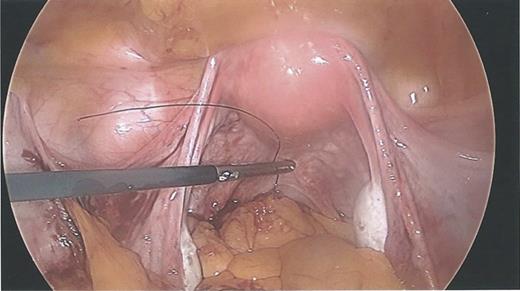

During the hysteroscopy 4 weeks later there was no evidence of an IUCD into the uterine cavity and no evidence of a perforation site in the uterus (Fig. 1). A laparoscopy followed, locating the coil threads deep in the Pouch of Douglas, with the IUCD perforating through the sigmoid colon into the lumen (Fig. 2). The IUCD was retrieved laparoscopically and the defect in the sigmoid colon was repaired by stapling the tear (Fig. 3).

Laparoscopy showing a sigmoid colon post-repair after removal of coil.